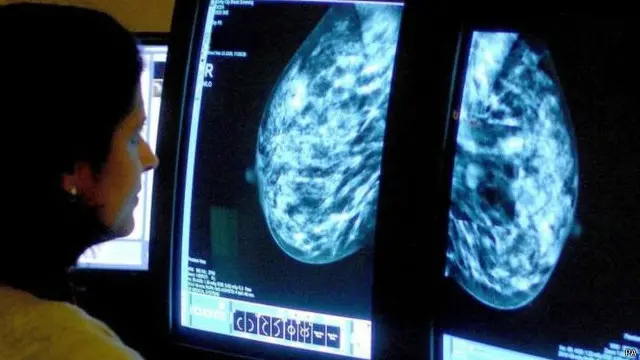

图像来源,PA

根据英国癌症关怀慈善机构麦克米兰癌症援助的一份报告说,目前英国有17万多癌症患者在被诊断癌症之后,存活了几十年,最多达40年。